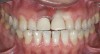

3. Excessive Shear and Tensile Stress Risk Assessment

Figure 3  Image demonstrating deep overbite in which shear and tensile stresses would be at least medium. Bonded porcelain would require maintenance of enamel and an occlusal strategy to reduce leverage on the teeth.

Figure 3